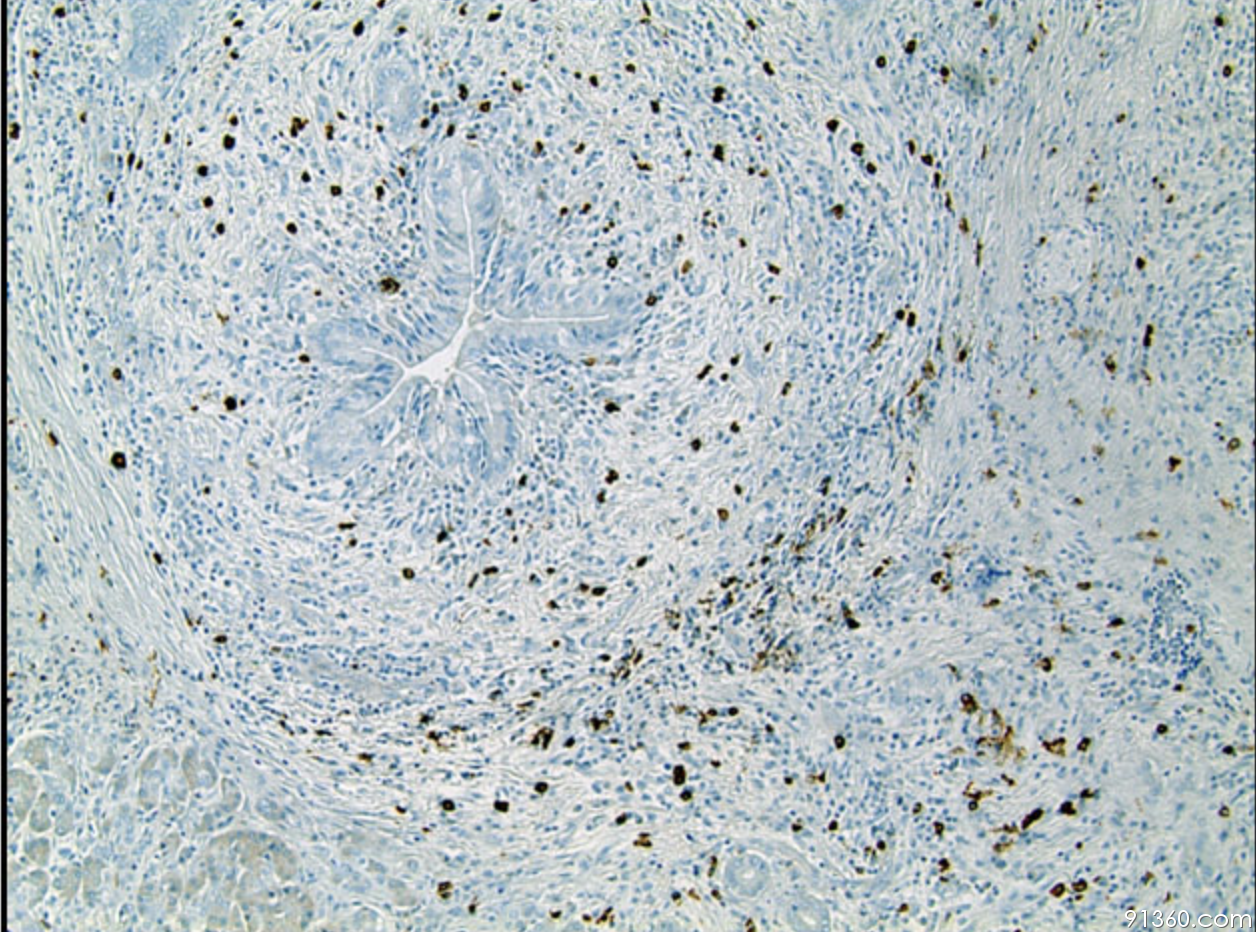

lgg4

43例igg4相关性疾病患者临床诊治分析